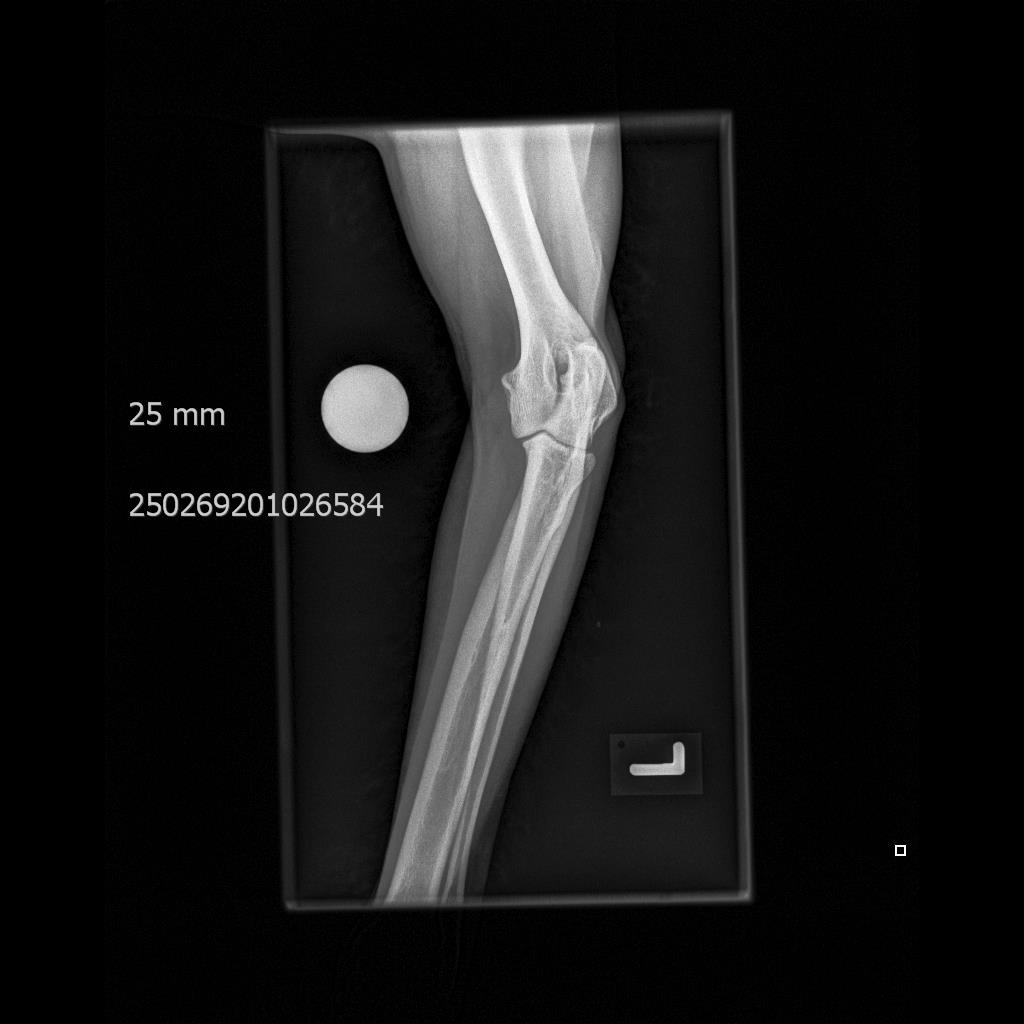

• Frakturbeurteilung